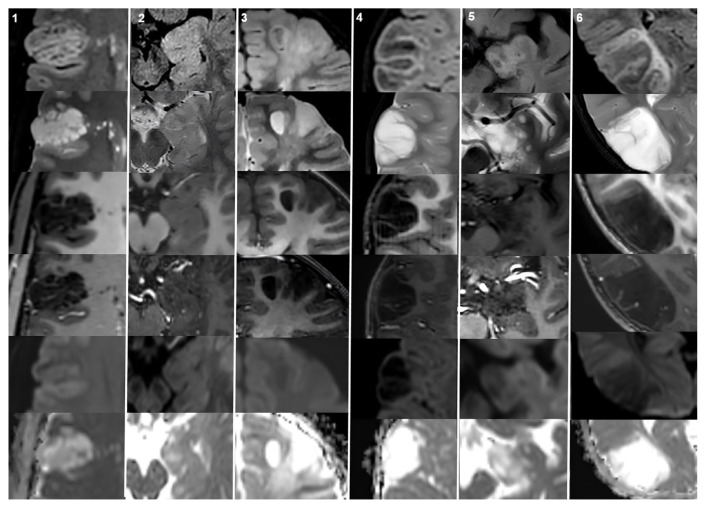

Results: There were 21 patients in the MVNT group and 20 patients in the DNET group. Headache was the most common symptom in patients with MVNTs (61.9%), whereas seizures were more prevalent in those with DNETs (70%). The most frequent locations for the MVNTs were the frontal and parietal lobes (66.6%), while DNETs were most commonly located in the temporal lobe (60%). All the MVNTs were hyperintense in both fluid-attenuated inversion recovery (FLAIR) and T2-weighted imaging (T2WI). All the DNETs were hyperintense on T2WI. However, on FLAIR, seven (35%) of the DNET lesions were hyperintense, while the remaining 13 lesions showed mixed signal intensity forming a bubbly appearance. Moreover, 20 of 21 (95.23%) MVNTs were hyperintense on diffusion-weighted imaging (DWI) (b800), with no apparent diffusion coefficient hypointensity in the lesions. None of the DNETs showed hyperintensity on DWI.

Conclusion: MRI findings, particularly those observed on FLAIR and DWI, may be helpful for distinguishing between MVNTs and DNETs, especially in cases where the differential diagnosis is challenging.